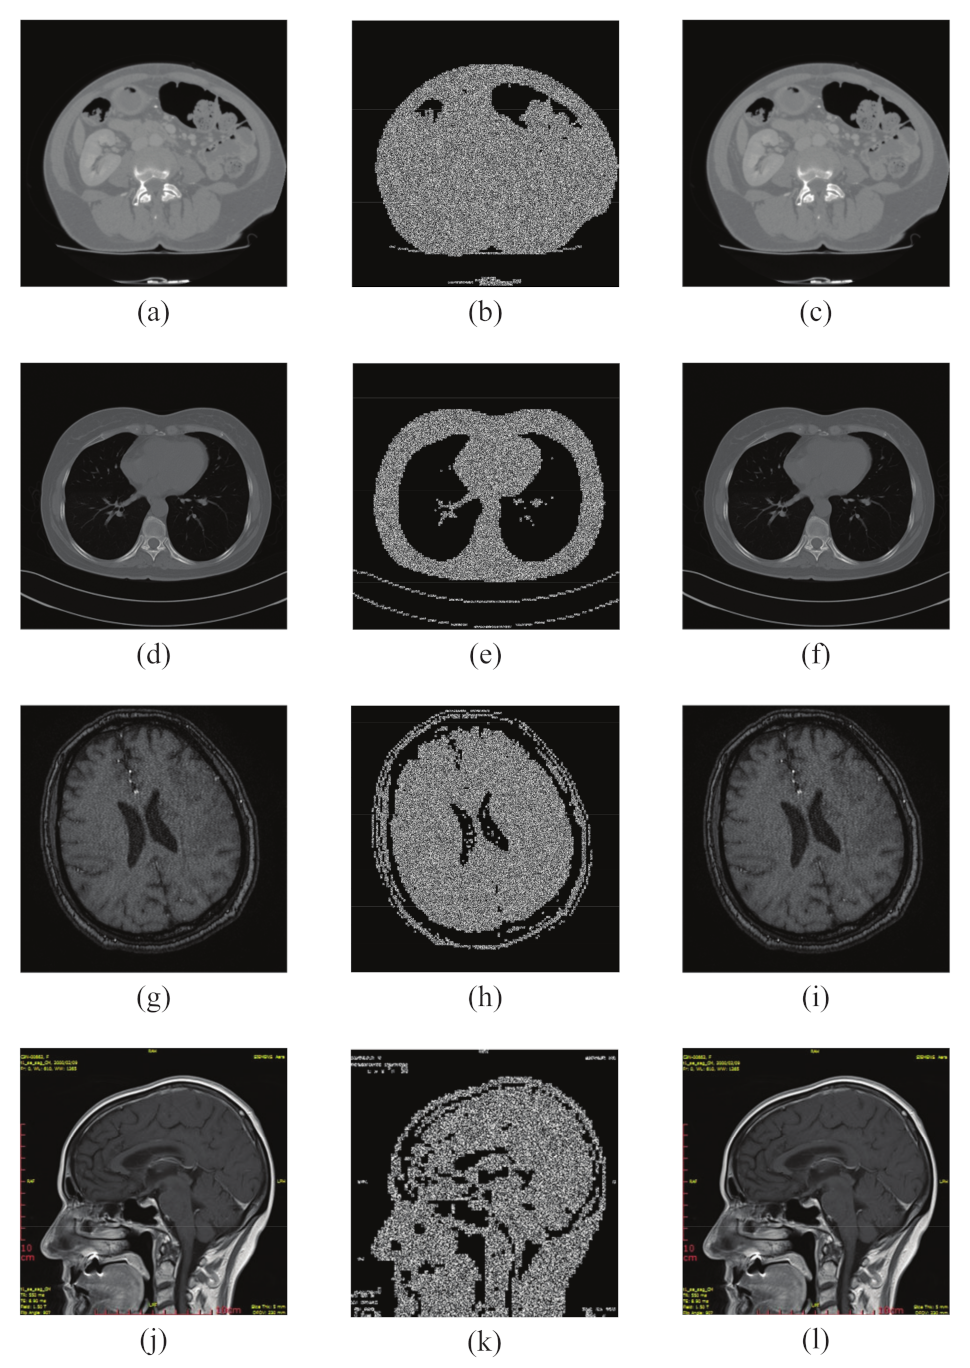

6.1. Simulation Results